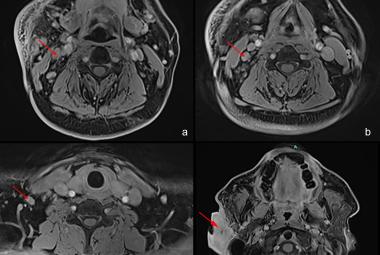

FIGURE 1: (A) Non-contrast CT brain demonstrated acute focal hemorrhage at the right occipital lobe withperihemorrhagic hypodensity extending to the right parieto-occipital region; (B) Subsequent CT venography in axial plane revealed thin linear isodensity within the right transverse sinus; (C) CT venography in coronal plane confirmed the filling defect within the right transverse sinus, consistent with thrombus